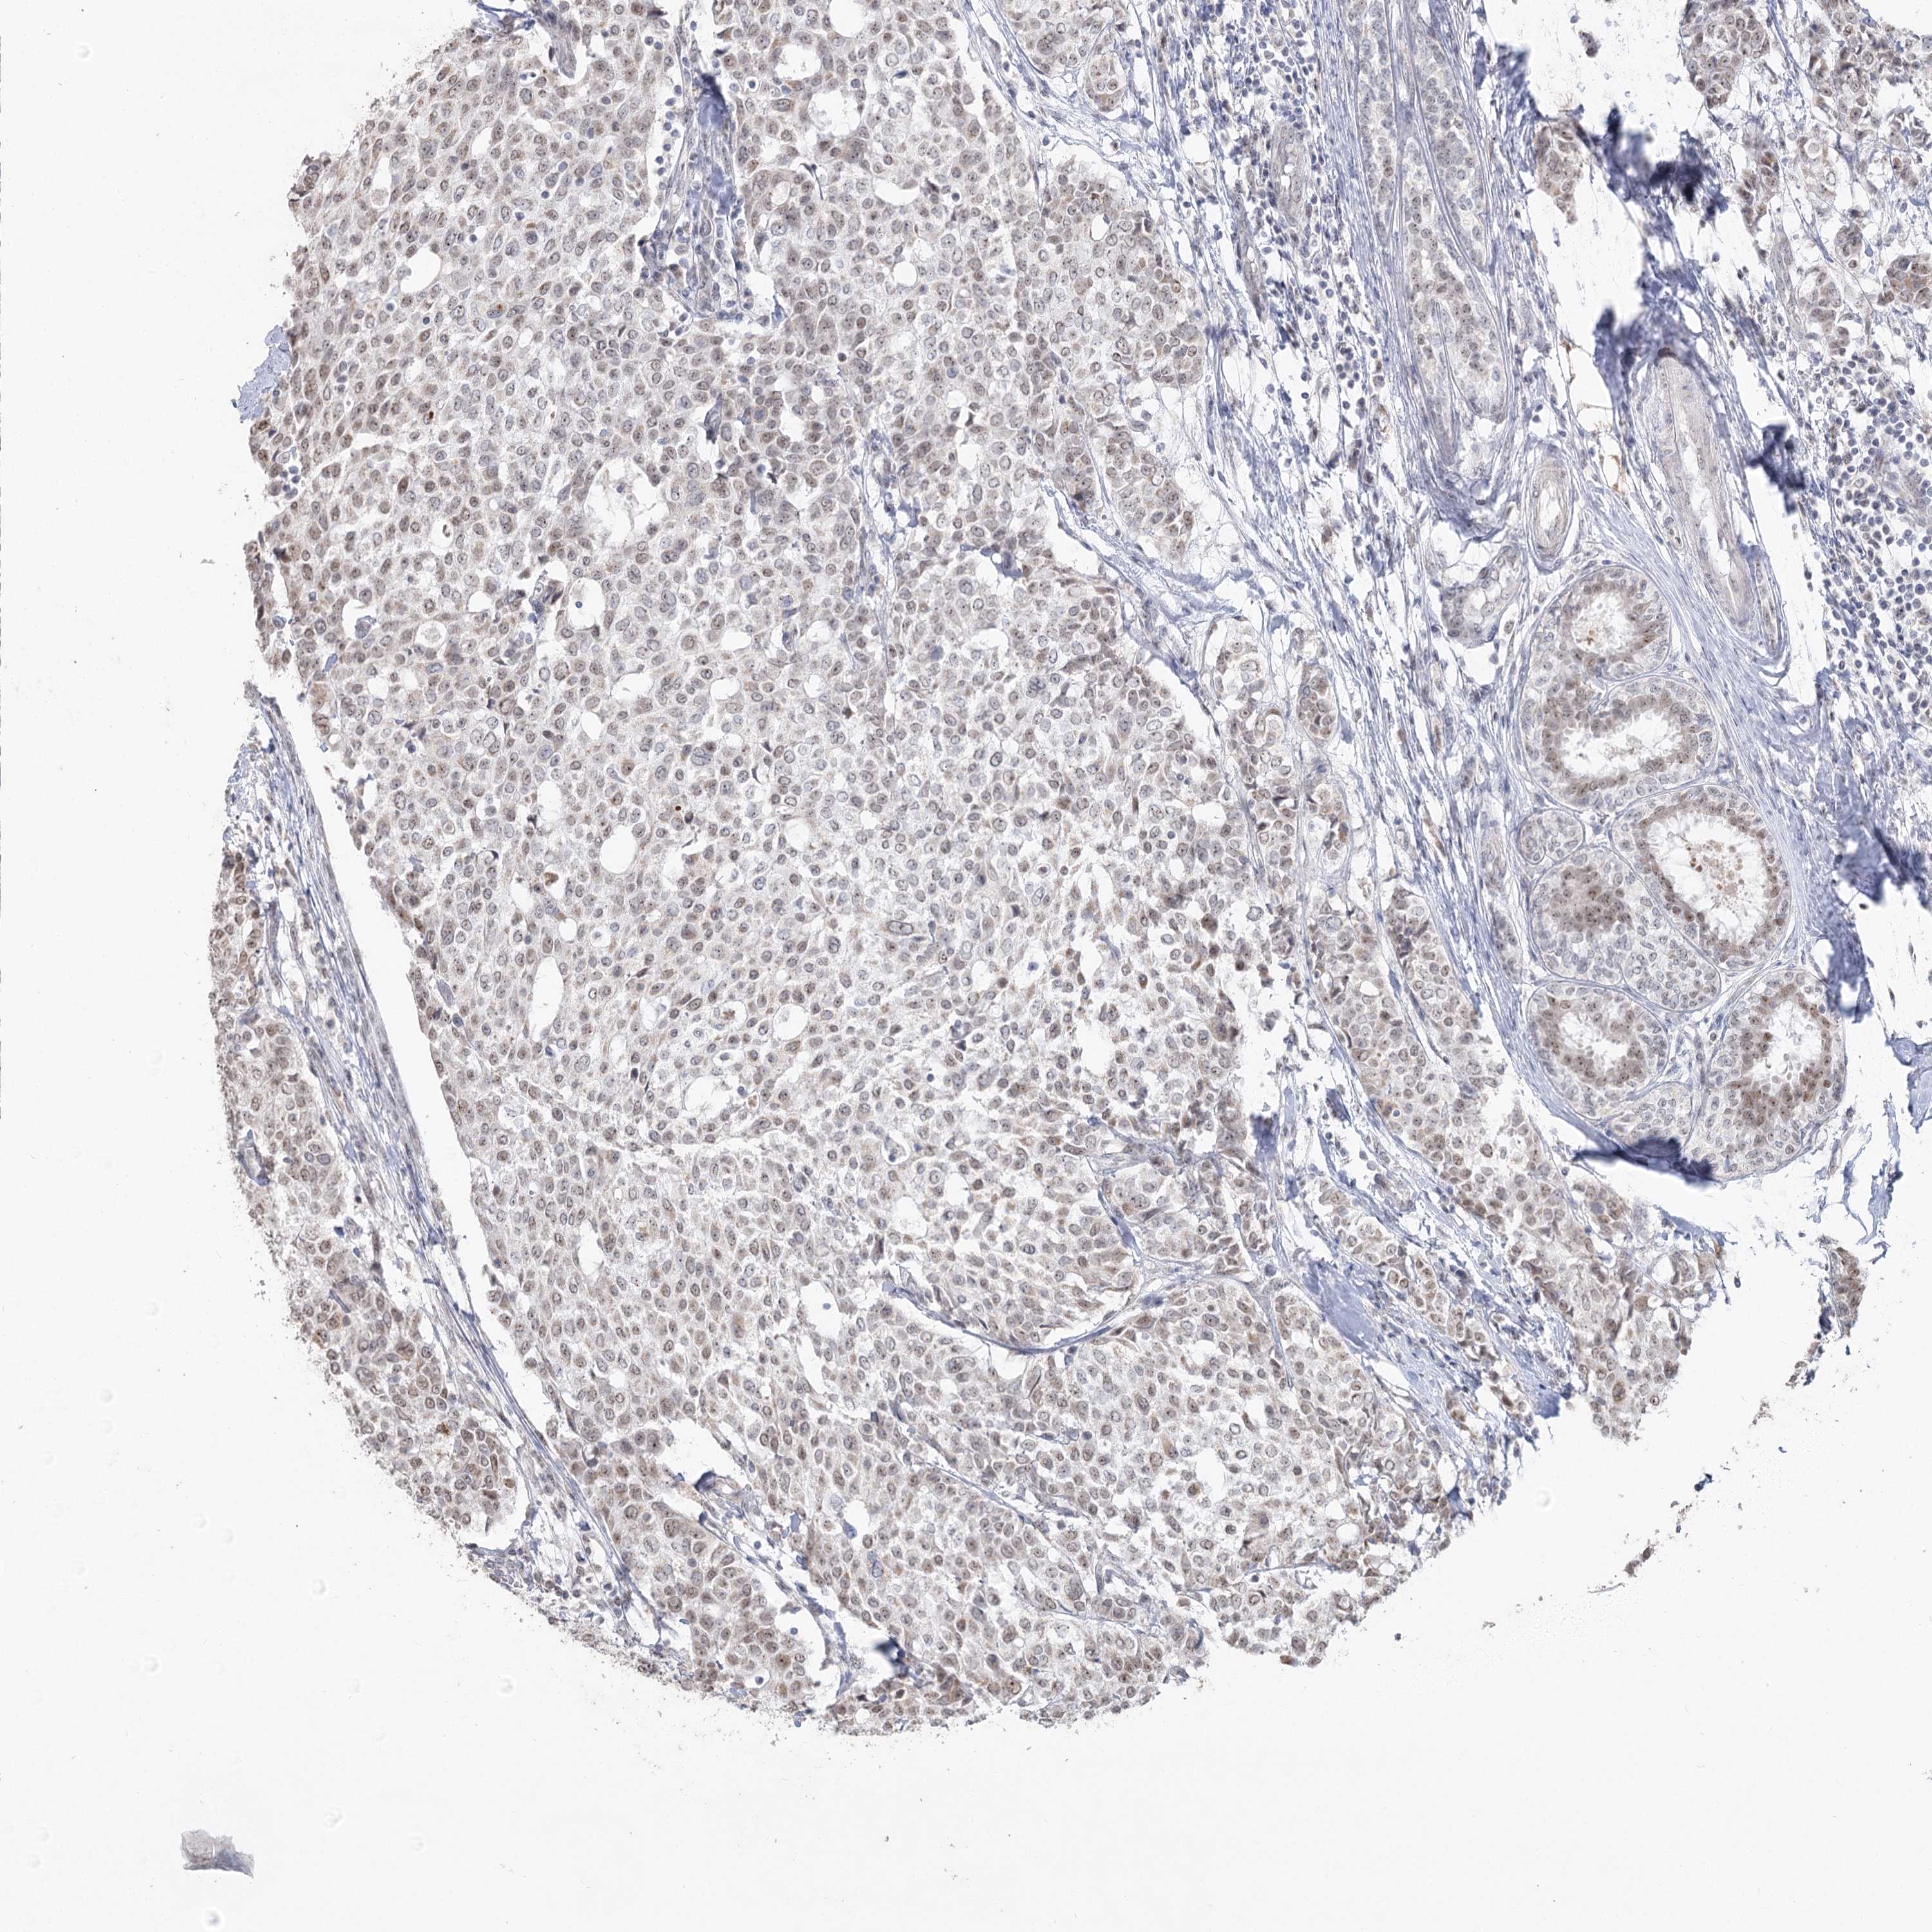

CANCER BREAST CANCER Show tissue menu

BRCA TCGA BRCA VALIDATION PROTEIN EXPRESSION

Breast cancer

Human cancer

RUFY4 is not prognostic in Breast Invasive Carcinoma (TCGA)